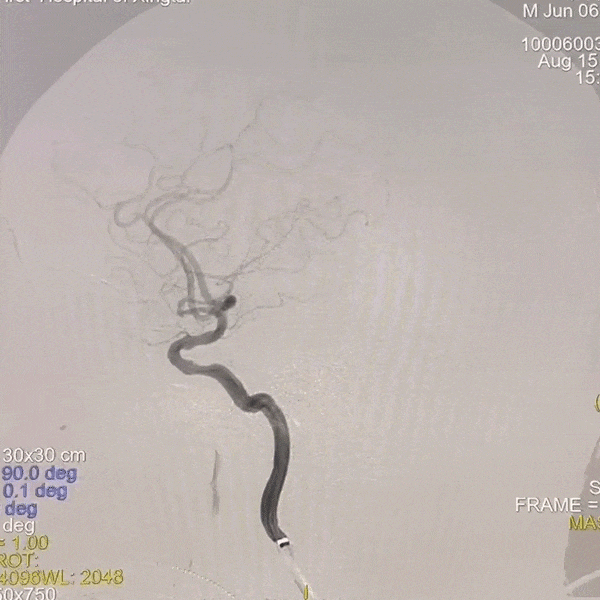

撤出多功能导管和短鞘,交换088输送导管至右侧锁骨下动脉近端,沿输送导管送入赛诺神畅APEX TRA GC™5F-130cm SIM2至主动脉弓,成袢后轻松超选入右侧颈总动脉,同轴沿SIM2导管将输送导管送入右侧颈总动脉,撤出SIM2导管,沿导丝将6F 115cm远端通路导管送至右侧颈内动脉C4段。

动脉长鞘怎么置入一技之“长”丨经桡及经股困难入路应用赛诺神畅APEX TRA GC™导引导管建立通路病例合集_https://www.jmylbn.com_新闻资讯_第33张

路图下上导丝、导管

动脉长鞘怎么置入一技之“长”丨经桡及经股困难入路应用赛诺神畅APEX TRA GC™导引导管建立通路病例合集_https://www.jmylbn.com_新闻资讯_第34张

SIM2导引导管超选右侧颈总动脉